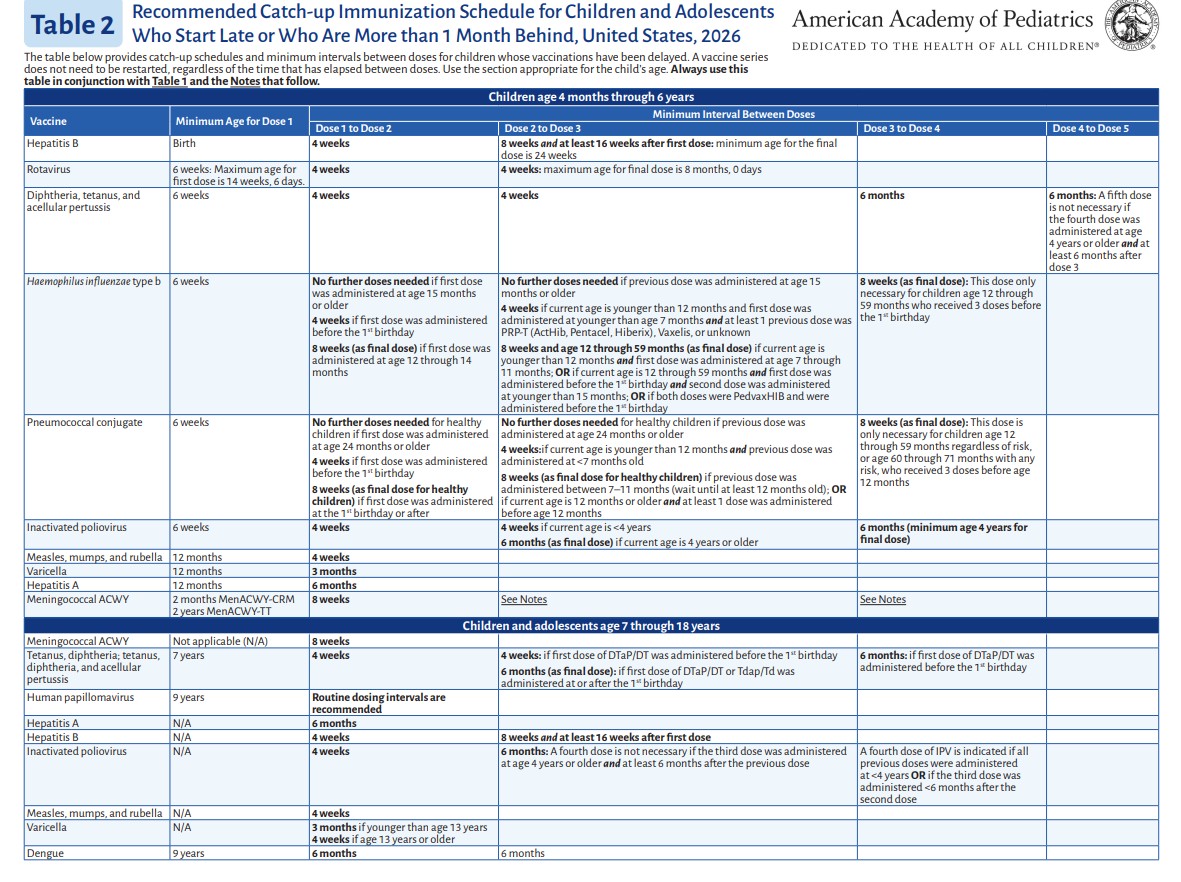

p 3